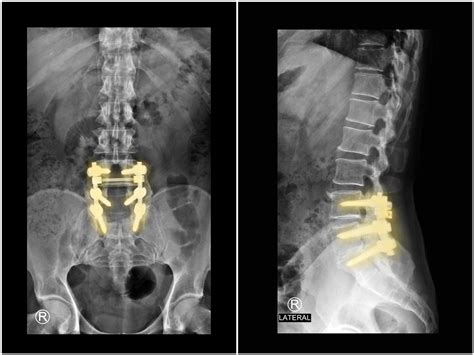

• Imaging Studies: X-rays, MRI, or CT scans to visualize the spine and determine the extent of the condition.

• Stabilization: Additional hardware, such as screws, rods, or plates, may be used to stabilize the spine and promote fusion.